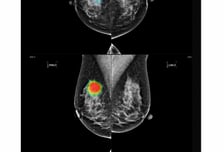

일본 정부가 X선 촬영으로 폐·유방·위암을 판독하는데 인공지능(AI)을 활용하는 방안을 검토한다. 국내에서는 의료 AI 업체 루닛이 일본 법인 '루닛 재팬'을 통해 검진·원격판독 시장을 직접 공략하고 있다. 24일 아사히신문 등에 따르면 일본 후생노동성은 전날 열린 전문가 검토회의에서 AI 기술 발전과 검진 비용 인하, 의사 부담 완화 등을 위해 1차 판독을 AI에 맡겨도 정확성이 유지될 수 있는지 검증하기로 했다. 현재 일본은 폐암 등 암 검진에 X선 촬영 결과를 2명 이상의 의사가 판독하도록 권고하는데, 이를 AI로 대체할 수 있는지 판단한다는 것이다. 구체적인 검증 기간과 방법은 아직 정해지지 않은 것으로 알려진다. 국내에서는 루닛이 지난달부터 일본 법인인 루닛 재팬을 통해 검진·원격 판독 시장의 직접 판매에 나선 상황이다. 기존에 후지필름과 파트너십을 통해 판매해왔던 데서 직접판매 체계를 정립, 병원 시장은 기존 파트너십 판매 전략을 유지하고 AI 도입 니즈가 큰 검진 및 원격 판독 시장은 루닛이 직접 고객을 발굴, 판매하는 '투 트랙 전략'을 적용했다.